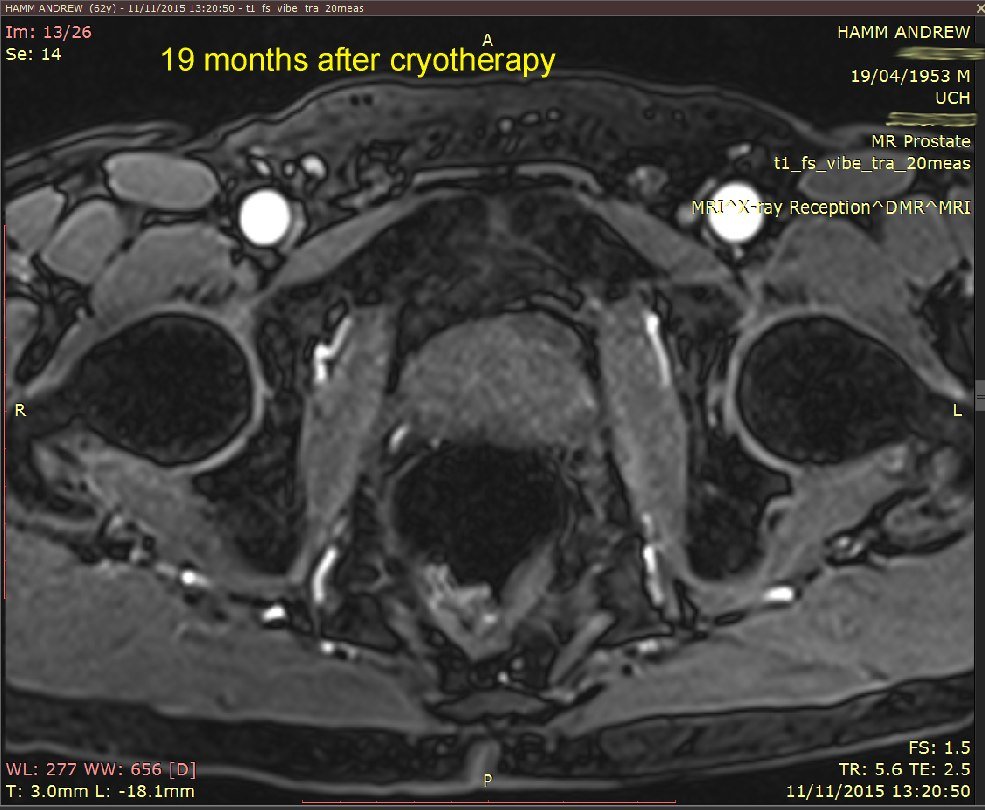

I've put 3 MRI images taken in November 2015. Compare these with my earlier ones below that, from 24 November 2014. Whilst not commenting specifically on these, the consultant said that the overall MRI had not revealed any significant (observable) prostate cancer.

18-day and 7-month MRI and PSA comparison - see image below.

Explanation: my prostate is roughly outlined in RED.

The original location of the tumour is roughly outlined in YELLOW on the 18-days image.

The ablated area is outlined in GREEN on the 18-days image.

These results show:

The ablated area has shrunk to (I presume) no volume at all.

My prostate volume has reduced by 5cc, which is pretty close to the 5cc volume that Emberton estimated would be ablated.

My PSA has rougly HALVED. The present PSA of 3.1 is within the range expected for a man of my age (61 years) who does not have significant prostate cancer.

My conclusion: Success! Cancer treated*.